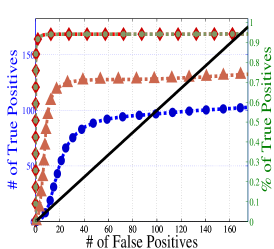

To understand the performance of this standard method, we present a small preview of our simulation study discussed later in Section 4. Briefly, we assume that each subject graph in group follows a small-world structure on nodes; in group , there are in addition 150 differential edges, meaning that and for all differential edges, . We generate data according to this model with time points and subjects in each group. Figure 1 illustrates the results of this standard approach as well as our new procedure, , which we will introduce later in Section 3. Part (a) gives ROC curves for the number of false positives verses true positives as each sequential test is rejected; parts (b) and (c) give the adjacency confusion matrix illustrating where the true and false positive as well as false negative edges are detected in the graph structure.

Our motivating simulation shows that the standard approach performs terribly in terms of both error control and statistical power. While the magnitude of the poor performance of this approach may seem astonishing, the poor performance should come as no surprise: The inferential procedure (e.g. test statistics) of the standard approach assume a one-level model that would be appropriate when the subject graphs are fixed and known or directly observed quantities. When these subject networks are unobserved, however, and must be estimated from finite data, these one-level test statistics are incorrect for our two-level problem. Specifically for two-level problems, the variance of parameters estimated by incorrectly assuming a one-level models is underestimated. For our problem, the extra source of variability arises from the graph selection procedure; we discuss challenges associated with this subsequently in Section 2.2. Incorrect variance estimates, however, are not the only problem with the standard approach: A more subtle problem arises from the fact that the proclivities of graph selection procedures for the Gaussian graphical model lead to biased estimates of the edge proportions, . As discussed in Section 2.3 and seen in Fig 1, graph selection false positives and false negatives do not occur at random throughout the network structure, leading to biased group level estimates.

Hence, the first term represents variability across subjects in group and the second term represents the variability associated with the selection procedure within subject , a quantity that we assume to be constant across subjects in each group . Consider now what happens if our true model follows this two-level Beta-Binomial model, but as with the standard approach, we use a one-level Binomial model and associated two-sample test statistic. The variance is thus underestimated and the test statistic is overoptimistic. Then, when inference is conducted for the population mean , using the incorrect Binomial model leads to inflated Type I error rates; this behavior has been well-documented (Weil, 1970; Liang and Hanfelt, 1994). Hence, failure to use the correct two-level model which accounts for the two levels of network variability partially explains the high error rates of the standard procedure observed in Figure 1.

In Figure 4 and Table 1, we present our main simulation results comparing to the two variations of our method and the standard approach for three network structures and Case I and II type differential edges. First for Figure 4, we report results in terms of operating characteristics averaged across 50 replicates with the number of true positives (y-axis) plotted against the number of false positives (x-axis) for each test statistic, rejected sequentially from largest to smallest in absolute magnitude. Overall, all of our methods and particularly yield substantial improvements over the standard approach in all scenarios.